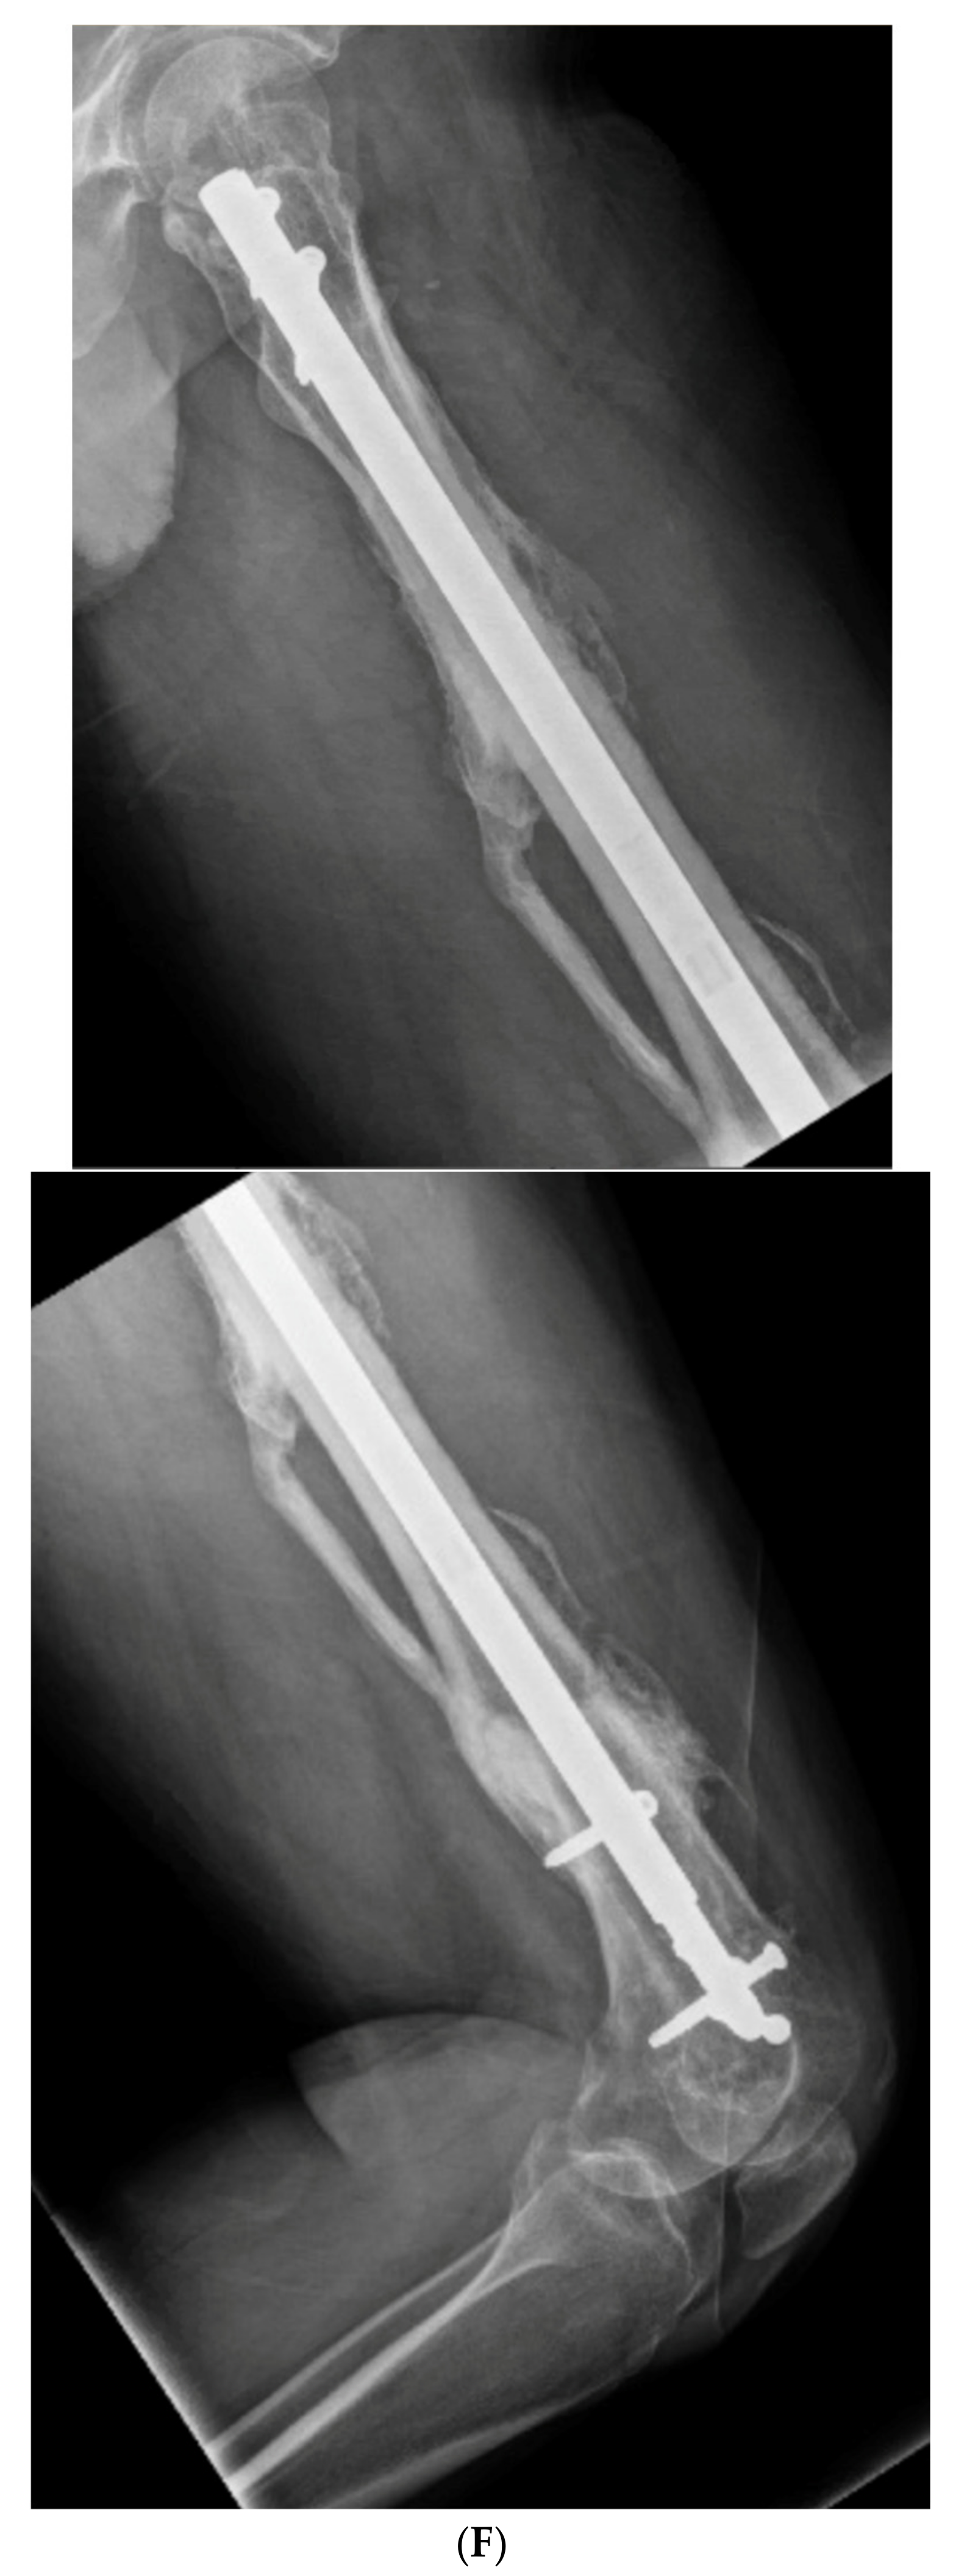

3.4. Case 4-Infected Malunion-Nonunion Femur Correction: True Dome Osteotomy

A young adult male presented new-onset diabetic ketoacidosis and sepsis. The study revealed a large thigh abscess circumferentially surrounding the left femur (Figure 9A). No other source was identified during workup. The patient underwent multiple debridements, and initially, a cortical window was made for the egress of intramedullary purulence. Subsequent debridements revealed extensive osteomyelitis. During debridement with intramedullary antibiotic nailing, the femur fractured and was eventually resected to attain source control (Figure 9B). A 13-cm segmental defect was stabilized using an antibiotic-coated locked nail with the surrounding antibiotic bone cement spacer Figure 9C). The CORA analysis revealed a five-degree varus deformity and no significant sagittal plane deformity. After source control with intravenous antibiotics and a 3-month course of oral antibiotics, the workup, including a biopsy and culture, resulted in no growth and no sign of ongoing infection. A bifocal true dome osteotomy with intercalary cortical allograft was chosen based upon a low likelihood of compliance with bone transport. A standard lateral approach elevating the vastus lateralus was used to access the femur. Reverse reamers and standard acetabular reamers were used for mating the bone surfaces (Figure 9D). The varus alignment was addressed using a blocking screw as the nail was passed; no gap was produced at the osteotomy due to its true dome shape. The dome osteotomy interfaces were autografted and compressed with a magnetic motorized nail, with additional compression at the subsequent outpatient visits (Figure 9E). The patient had soft tissue and allograft interface healing without incident and returned to gainful employment (Figure 9F).

Figure 9.

(A) A young adult male presented new-onset diabetic ketoacidosis with sepsis. He was found to have a large spontaneous left thigh abscess, as seen on CT imaging. (B) Multiple surgeries resulted in a femur fracture and subsequent segmental resection of approximately 13 cm of the patient’s femoral diaphysis. (C) The patient eventually attained source control with resection, antibiotic spacer, and an antibiotic coated nail. Patient has a 5-degree distal varus deformity. (D) The patient underwent a true dome osteotomy of the proximal and distal ends of the allograft/host bone interfaces. Fresh frozen allograft preparation using a reverse reamer is shown prior to implantation. (E) Motorized compression of the construct was employed with early and subsequent compression. Four-month follow-up showed restored neutral alignment, incorporation/interface healing of the dome osteotomy sites, bone regenerate across the interfaces, normal lab markers, and return to gainful employment. (F) Twelve-month follow-up continued to demonstrate interface healing without infection recurrence.